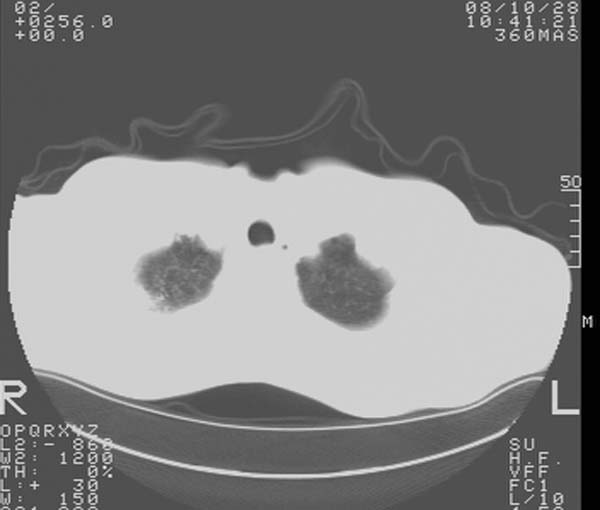

m,65y。半年前发现颈小结节,逐渐增多增大,现双侧耳后、颌下及颈部表浅淋巴肿大。胸片示双肺门增大。外院曾穿刺诊断为淋巴结核。在我科作胸腹部ct,我们觉得外院病检有误。现将图像上传请战友讨论。

纵隔内及腹膜后广泛淋巴结肿大,脾大,肝内似可见低密度影,结合病史半年前发现颈小结节,逐渐增多增大,现双侧耳后、颌下及颈部表浅淋巴肿大。考虑淋巴瘤。

纵隔,双肺门腹膜后多发淋巴结重大,非融合,肝脾轻度肿大,双肺野弥漫性小结节;考虑淋巴瘤,结节病可能性

纵隔内,双肺门、腋窝及腹膜后多发肿大淋巴结影,肺内小结节影,肝脾体积增大,支持淋巴瘤。肝内多发低密度影,考虑小囊肿。